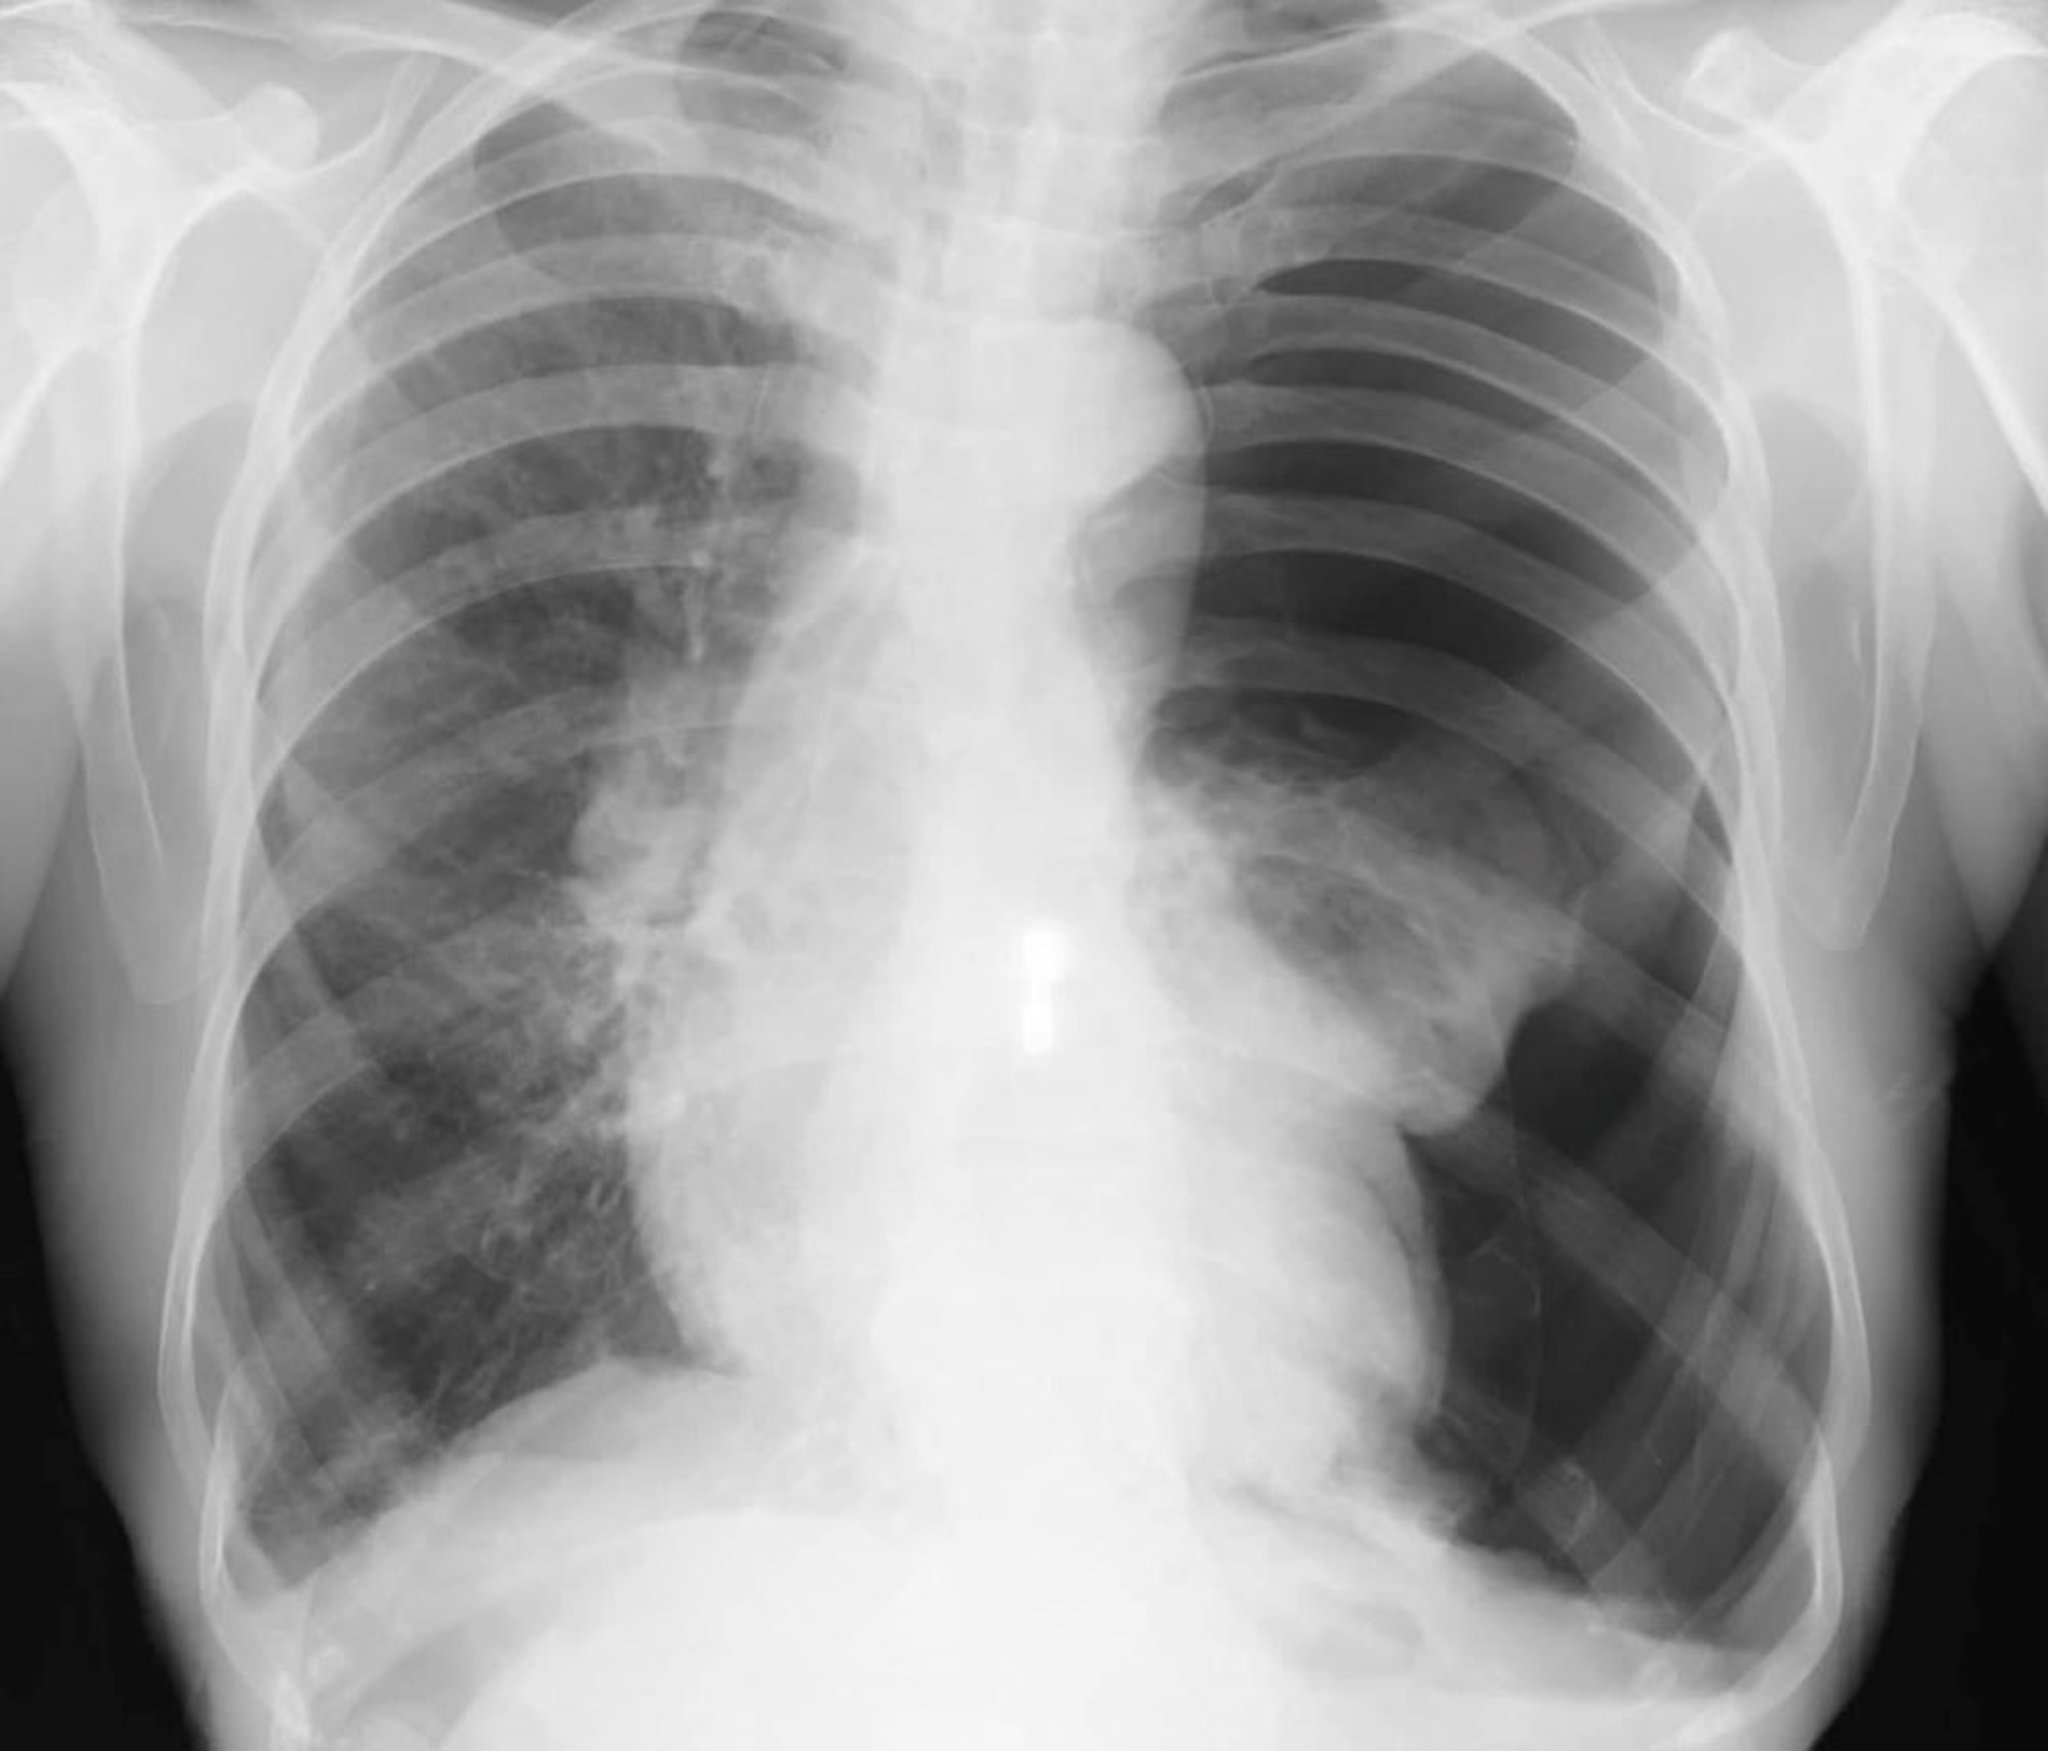

Le diagnostic est suspecté chez le patient dont l'état est stable mais qui a une dyspnée ou une douleur thoracique pleurale et est habituellement confirmé par une radiographie du thorax inspiratoire verticale. La densité du tissu pulmonaire est augmentée si des clichés expiratoires sont obtenus, augmentant ainsi la différence de contraste entre l'air dans l'espace pleural et le tissu pulmonaire adjacent (qui a moins d'air en raison d'une combinaison de l'état expiratoire et de tout collapsus). La présence d'air radiotransparent et l'absence des marques du poumon juxtaposées entre un lobe ou un poumon condensés et la plèvre pariétale sont diagnostiques du pneumothorax. Une déviation de la trachée et un refoulement médiastinal peuvent se produire en cas de grands pneumothorax. Le diagnostic peut également être fait par échographie au lit du malade si la maladie pulmonaire sous-jacente n'empêche pas une visualisation adéquate.

Les petits pneumothorax (p. ex., < 10%) sont parfois invisibles sur la radiographie thoracique. Chez les patients chez qui on suspecte un pneumothorax, les structures pulmonaires doivent être suivies jusqu'à la limite de la plèvre sur la radiographie du thorax. Même les pneumothorax importants peuvent ne pas être évidents sur les radiographies en décubitus dorsal, et le signe du sulcus (sillon) profond (un angle costophrénique anormalement profond) doit être spécifiquement recherché, car il peut être le seul signe de pneumothorax sur la radiographie chez un patient en décubitus dorsal. Les conditions qui imitent le pneumothorax sur la radiographie comprennent les bulles d'emphysème, les plis cutanés, les draps pliés, et le chevauchement des marques d'estomac ou d'intestin sur les champs pulmonaires.